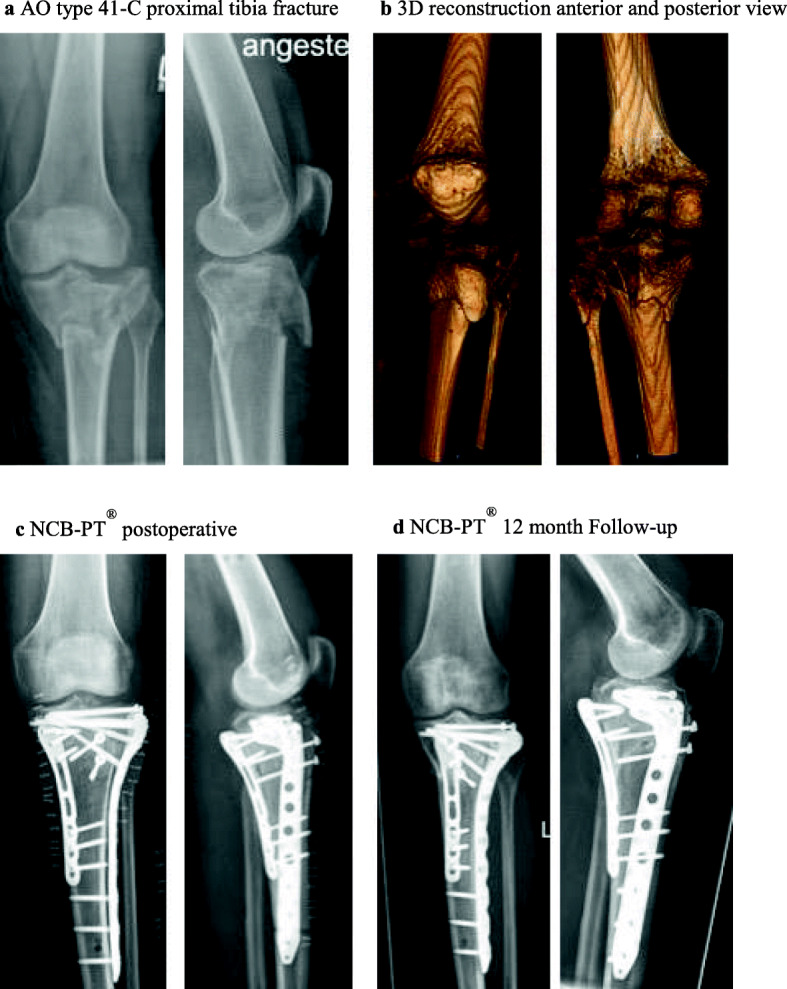

Fig. 1.

This figure shows an exemplary case of a 64-year old patient treated with a NCB-PT® system. The patient suffered from a AO type 41-C proximal tibia fracture (a-b) after a skiing accident. Initial fixation with an external fixator allowed the soft tissue to consolidate. Due to soft tissue concerns, a staged procedure was chosen for definitive reconstruction. In the first step we conducted a plate osteosynthesis after reduction from posteromedial with a Synthes LCP and the patient in prone position. For the second step we performed a standard anterolateral approach. After a horizontal arthrotomy and visualisation of the entire lateral plateau we elevated the central indented fragment and supported it with an allogeneic cancellous bone graft. After reaching a satisfactory reduction of the lateral compartment we inserted a 7-hole NCB-PT® plate as well as two proximal 4.0 mm lag screws. In a final step we performed a refixation of the tibial tuberosity with two 4.0 mm lag screws The presented images show the postoperative radiologic controls after the final surgery (c) and the image of our radiologic follow-up one year after surgery for NCB-PT® patients (d)